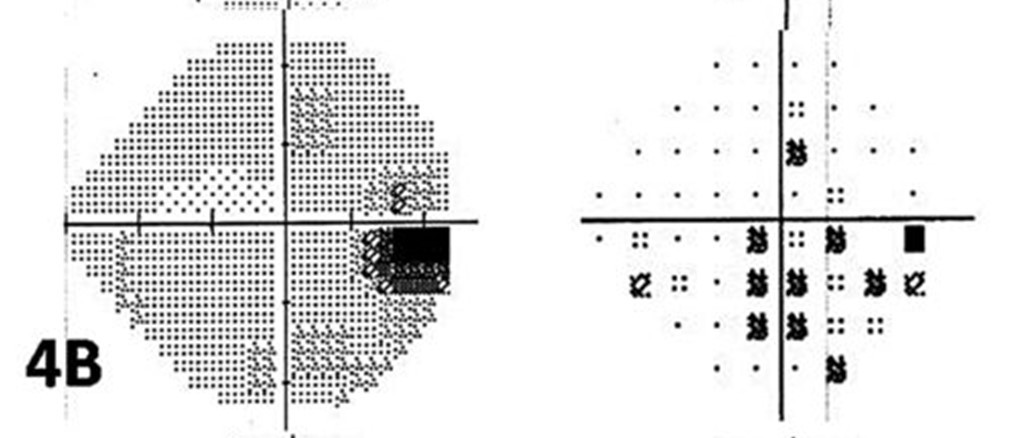

Advanced arcuate

Early arcuate

Nasal step